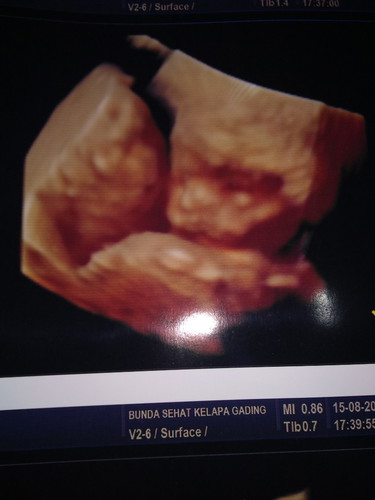

Alhamdulillah kesampaian usg 4D baby NO2 , kemarin kehamilan pertama mau 4D sayang d pikir2 harganya, skrg udah ada yg murah d bawah 300k tapi pelayanan tidak mengecewakan ,puas dokter yang ramah dan yg lain nya ramah 2 .. semoga JK nya gak berubah ? amiin . Tapi 22weeks kemungkinan ada berubah gak ych mom ???